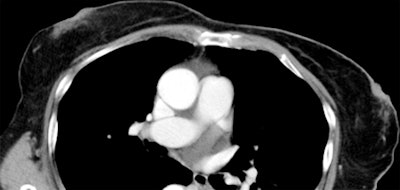

Axial CT images of a 70-year-old woman with grade 1 CT breast density (above) and a 42-year-old woman with grade 4 (below). All images courtesy of Radiology.